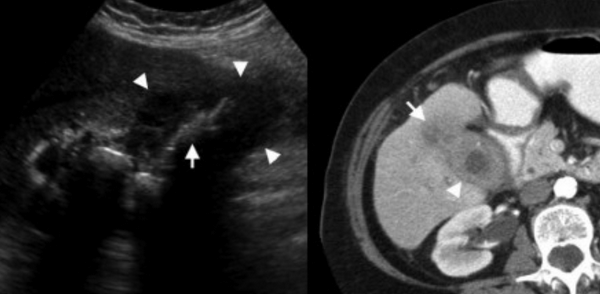

Выше представлено КТ пациента 71 года с ксантогранулематозным холециститом. Постконтрастное КТ. Визуализируется утолщение стенки желчного пузыря с включениями, которые соответствуют абсцессу или фокусам воспаления.

УЗИ (слева) и КТ (справа) желчного пузыря. На УЗИ ярко выраженное утолщение стенки желчного пузыря (указаны белыми стрелками). Множественные камни в просвете желчного пузыря (указано стрелкой). Компьютерная томография с контрастным усилением. На КТ визуализируются утолщение стенки с внутристеночными гиподенсными включениями. На КТ также выявлено, что процесс распространился на печень (указано стрелкой).